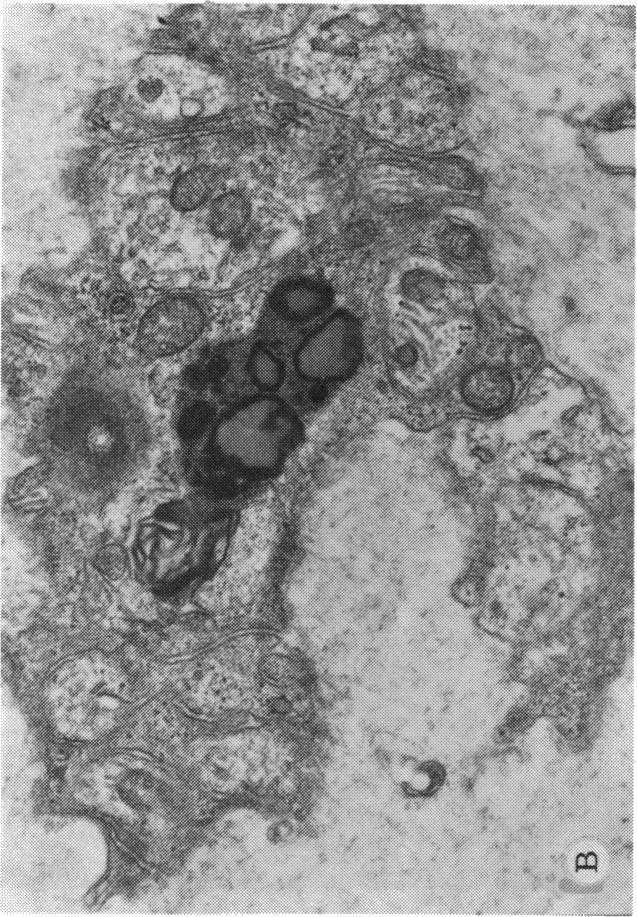

In 1937 Bietti reported a tapetoretinal degeneration with associated corneal deposits at the limbus. The hallmark of the disease was the crystalline characteristics of the retinal spots as well as those at the corneal limbus. Bagolini and Ioli-Spade in 1968 presented a 30 year follow-up on Bietti's cases and presented six additional cases. The present report delas with this entity in Orientals, a Chinese woman and a Japanese man. Corneal and conjunctival biopsy from the female patient revelaed a lipid deposition in both fibroblasts and epithelium. The term "crystalline retinopathy" has been added to the description of this entity since it defines the most characteristic feature of the syndrome.